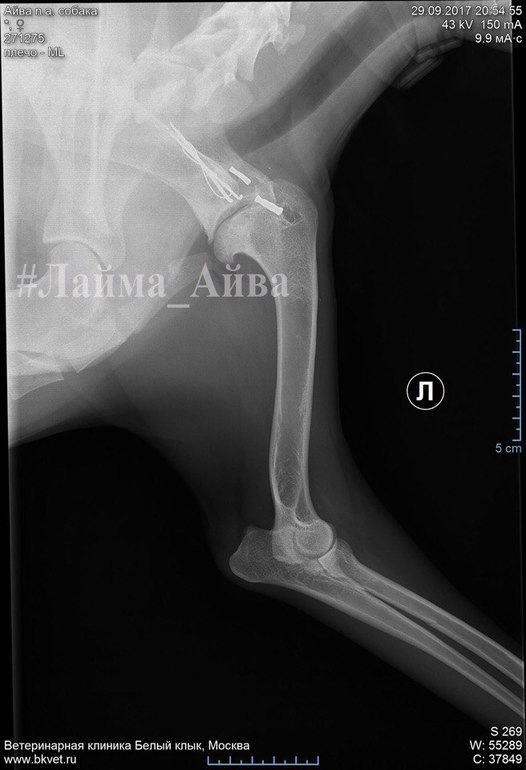

Все уже забыли про Лайму...НО СЛУЧИЛАСЬ КРИТИЧЕСКАЯ СИТУАЦИЯ, поставлен диагноз: ОСТЕОАРТРИТ плечевого сустава. АТРОФИЯ МЫШЦ плечевого пояса. НЕОБХОДИМА ОПЕРАЦИЯ...😭😭😭 Лайма хромает и ей больно...

Я давно не просила вас о помощи ни с передержкой,ни с кормом,пыталась справляться своими силами,понимая,что у всех куча животных более больных и тяжелых... Кто знает историю Лаймы с самого начала,помнит,когда мы ее нашли,лапа была сломана,прооперировали,но вот спустя год последствия на эту же лапу продолжаются... СРОЧНО НУЖНА ОПЕРАЦИЯ АРТРОДЕЗ ЛЕВОГО ПЛЕЧЕЛОПАТОЧНОГО СУСТАВА❗️ Принимал доктор Комаров А.А.

клиника "Белый Клык"

Оперироваться будем у хирурга Карелина М.С. Стоимость операции нам выходит примерно в 30-35.000 рублей